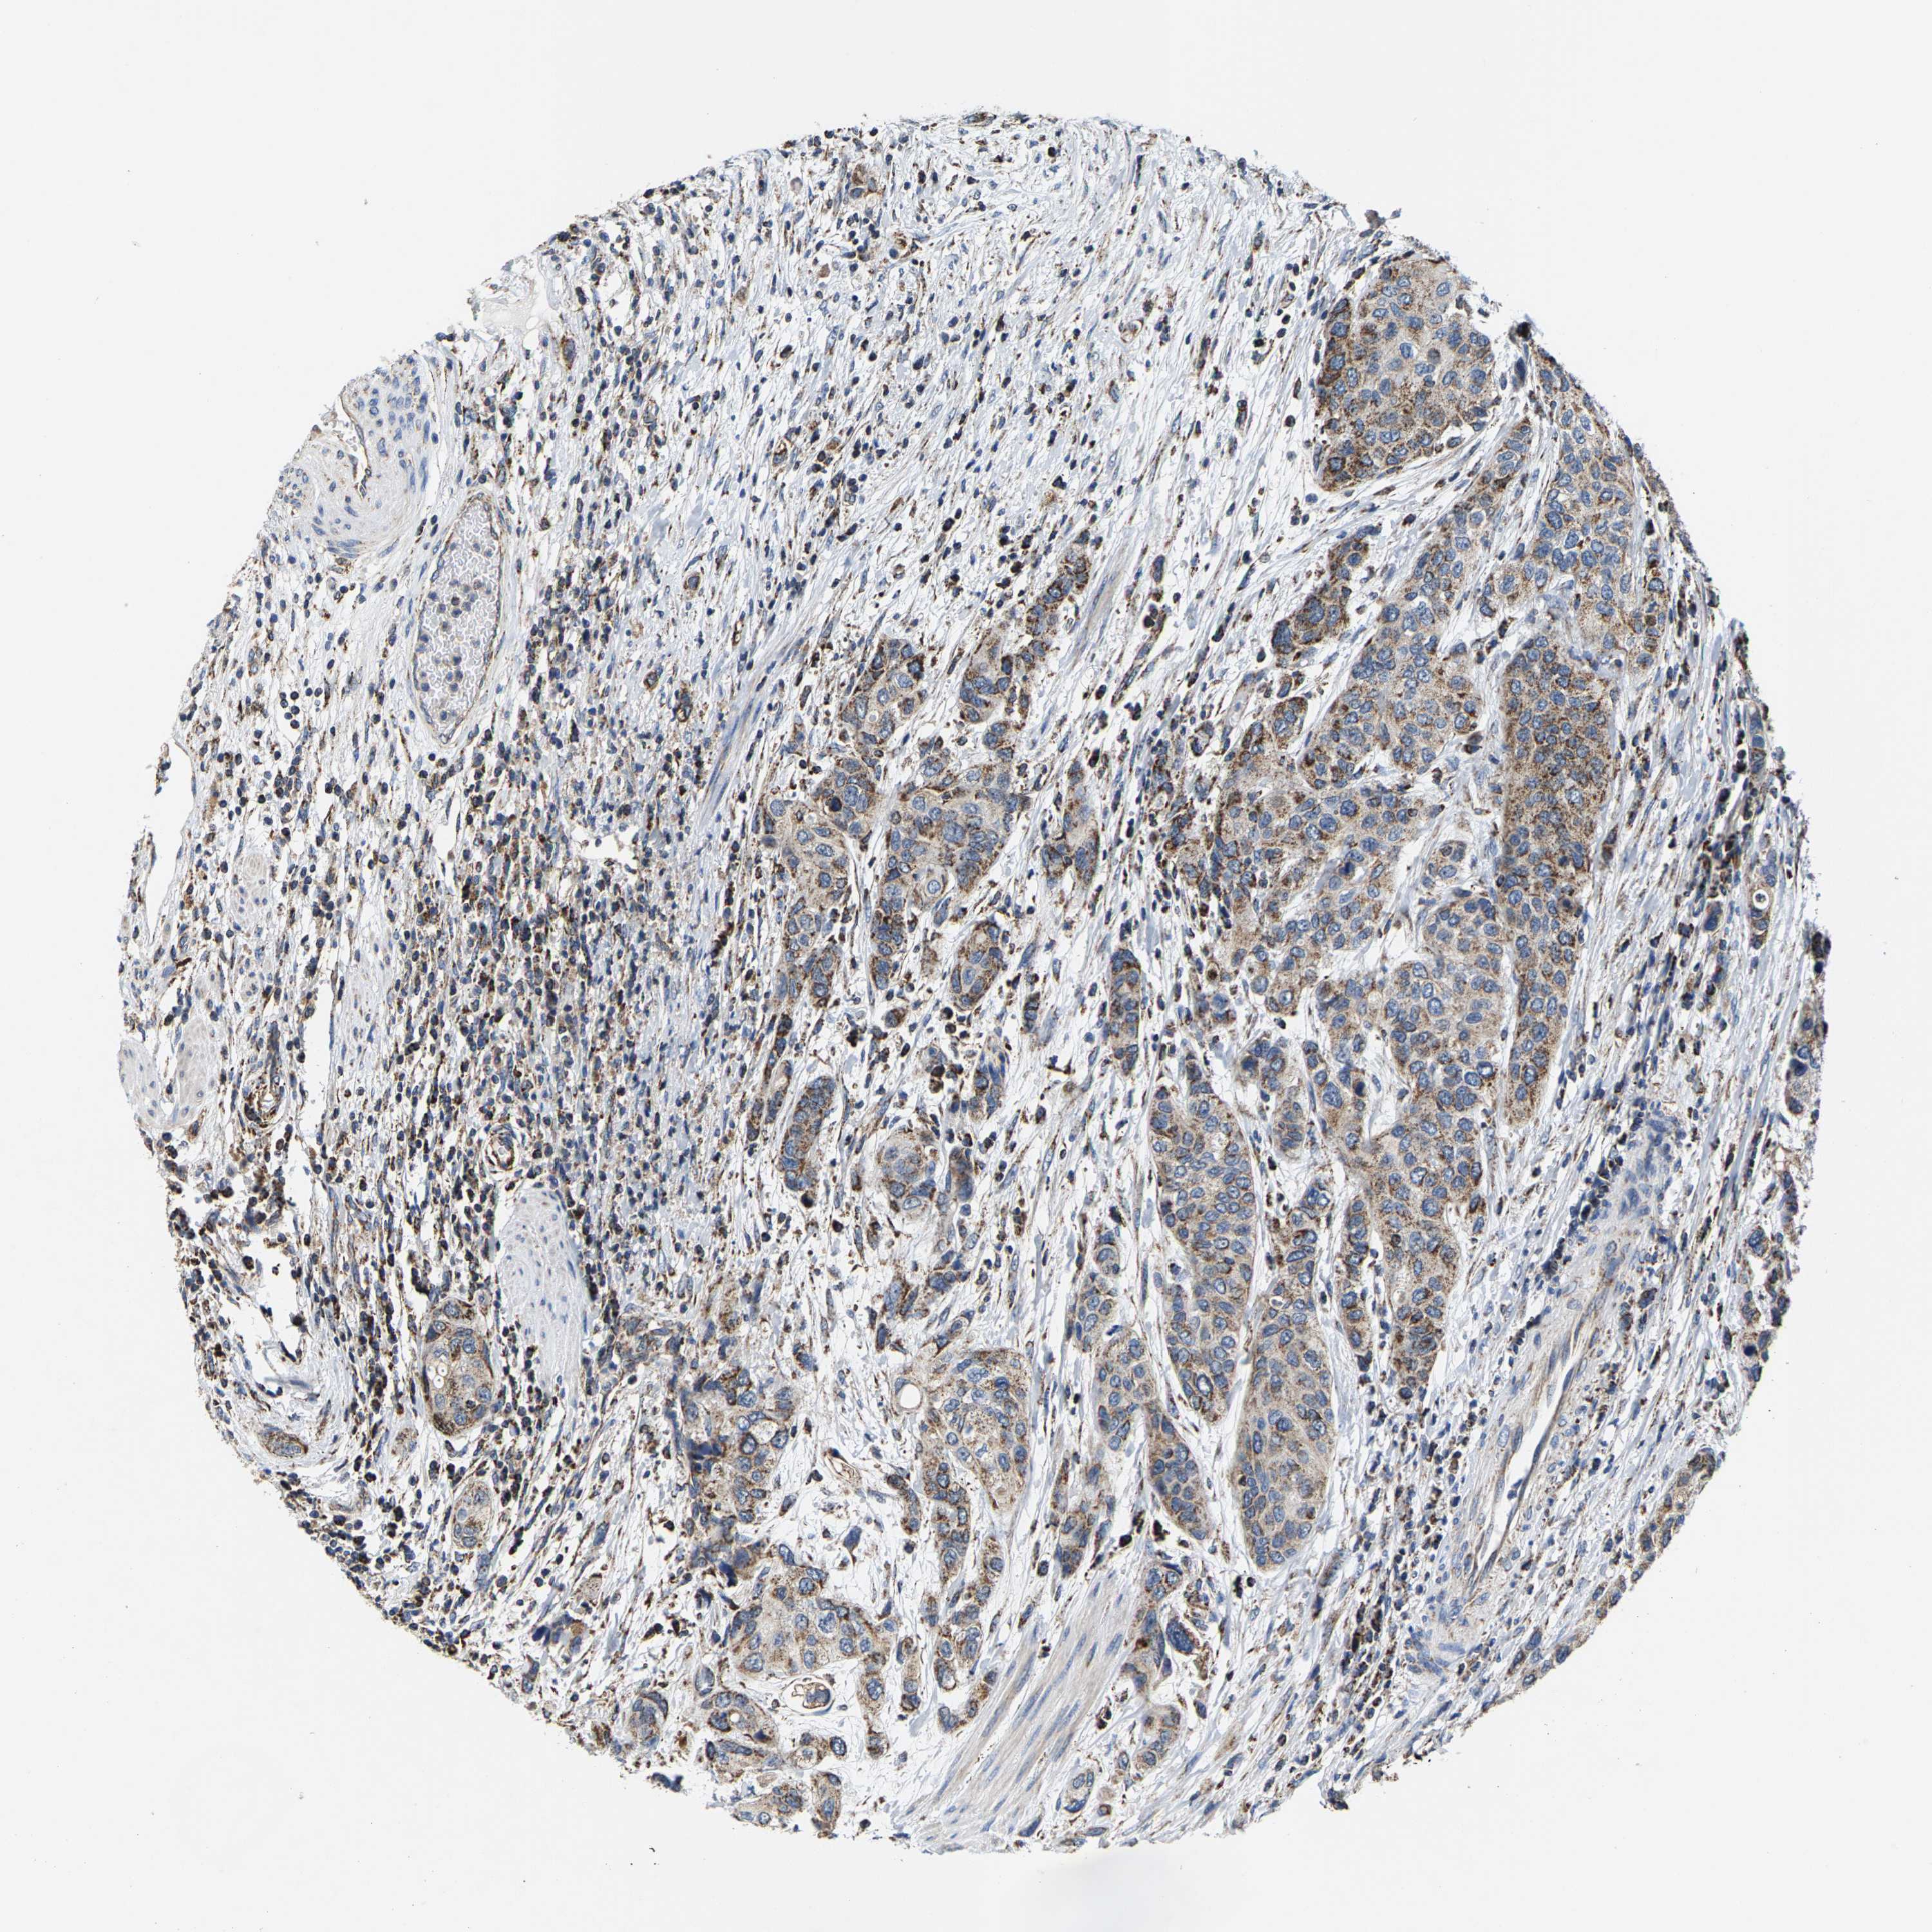

UROTHELIAL CANCER - Protein expressioni

A mouse-over function shows sample information and annotation data. Click on an image to view it in a full screen mode. Samples can be filtered based on level of antibody staining by selecting one or several of the following categories: high, medium, low and not detected. The assay and annotation is described here.

Antibody stainingi

Antibody staining in the annotated cell types in the current human tissue is reported as not detected, low, medium, or high, based on conventional immunohistochemistry profiling in selected tissues. This score is based on the combination of the staining intensity and fraction of stained cells.

Each image is clickable and will lead to virtual microscopy that enables deeper exploration of all samples and also displays staining intensity scores, fraction scores and subcellular localization as well as patient and tissue information for each sample.

Antibody HPA020543

Antibody HPA020549

Staining

High

Medium

Low

Not detected

Intensity

Strong

Moderate

Weak

Negative

Quantity

>75%

75%-25%

<25%

None

Location

Nuclear

Cytoplasmic/membranous

Cytoplasmic/membranous,nuclear

Urothelial carcinoma, Low grade

Urothelial carcinoma, High grade